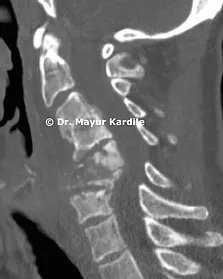

Cervical Myelopathy

65 yr gentleman